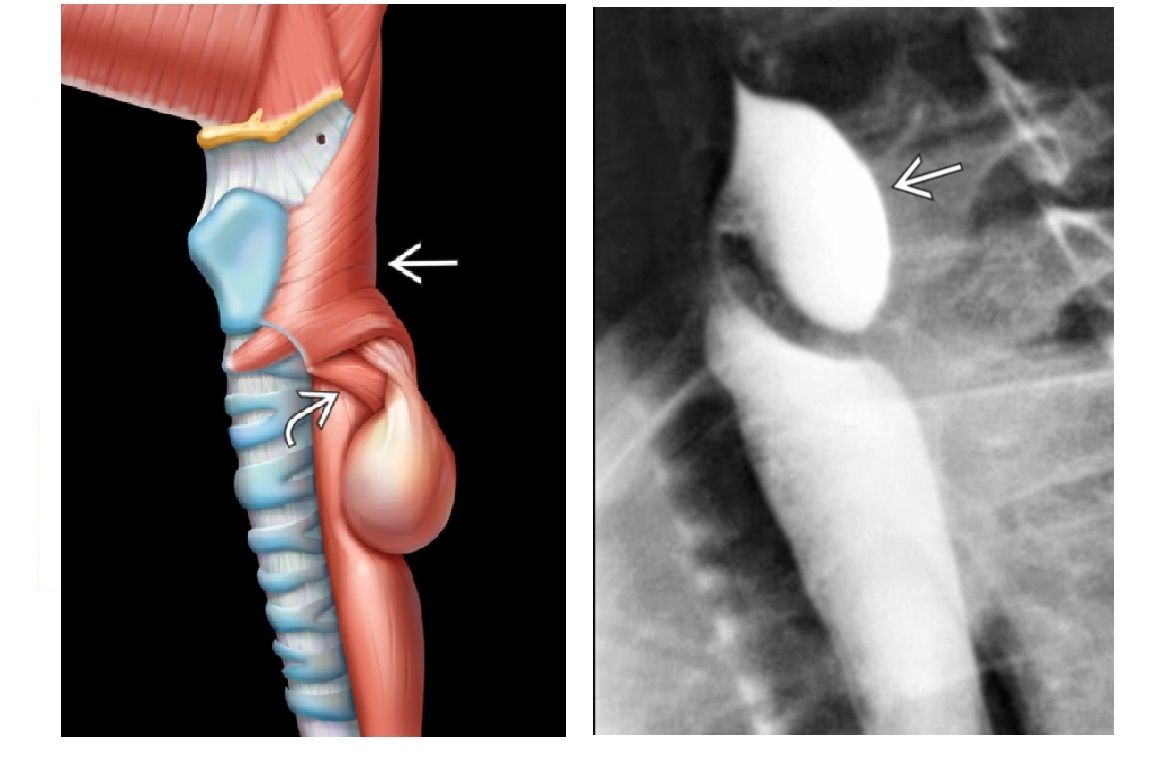

Outpouching with rounded contour posteriorly and the neck is above the cricopharyngeus muscle

A

Zenker Diverticulum

In hypopharynx!!!

Site of weakness is the Killian dehiscence - between the inferior pharyngeal constrictor muscle and cricopharyngeal muscle